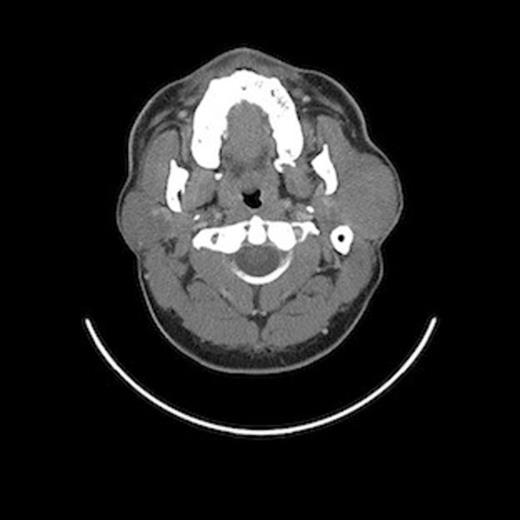

Postoperative prednisone taper treatment successfully decreased the size of the mass and was administered periodically as observation required. A repeat CT scan in July 2009 revealed a diffusely enlarged left parotid gland with complete resolution of the discrete mass (Fig.1–2). He was conservatively managed with periodic steroids until April 2010, when he complained of pain in the region and a feeling of gradual increase in size. A left parotidectomy was performed in May 2010, with removal of both the superficial and deep lobes of the parotid gland along with identification and preservation of the facial nerve.